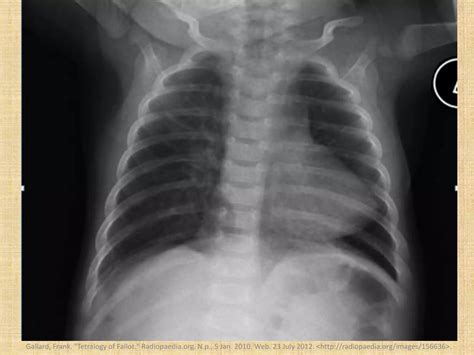

• xray boot shaped heart

• tetralogy of fallot

• tetralogy of fallot 4 defects

• boot shaped heart images